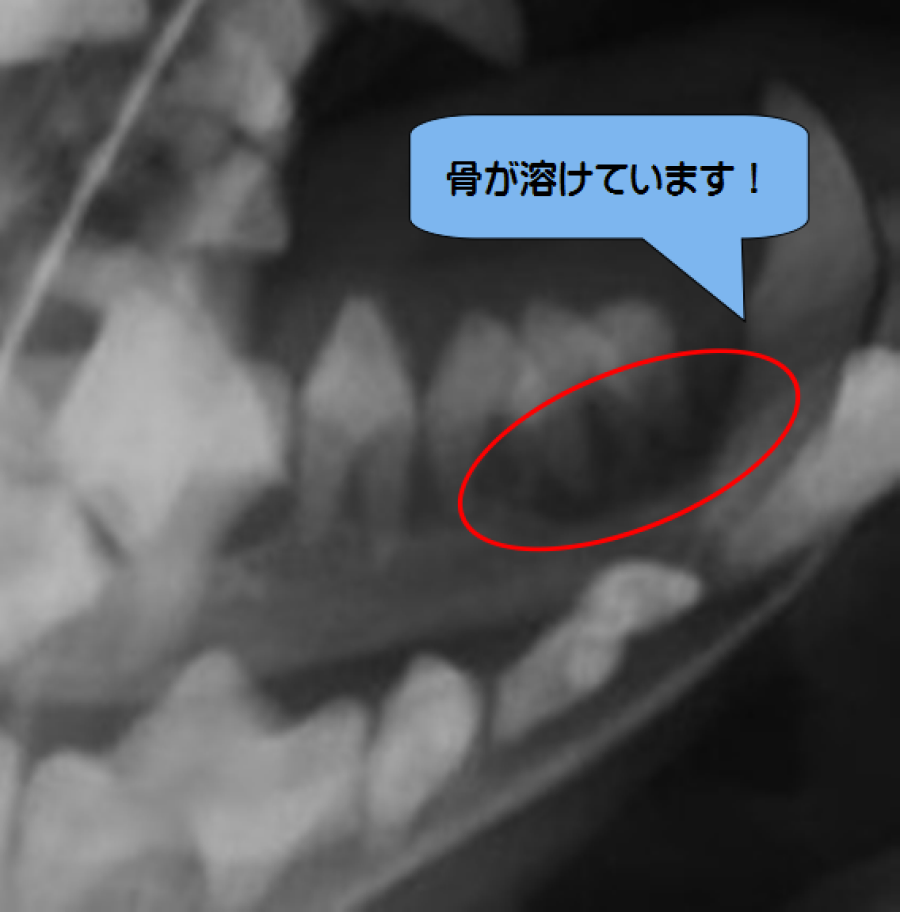

牧草をあまり食べずペレットに偏った食事を続けていると、奥歯が過剰に伸びて舌や頬の粘膜に刺さってしまうことがあります。痛みによる食欲低下から胃腸運動の停滞、胃腸にガスが貯まりさらに運動が停滞と悪循環になり命に関わることもあります。

過剰に伸びた歯は、麻酔下で削る必要があります。同時に食事管理も行います。